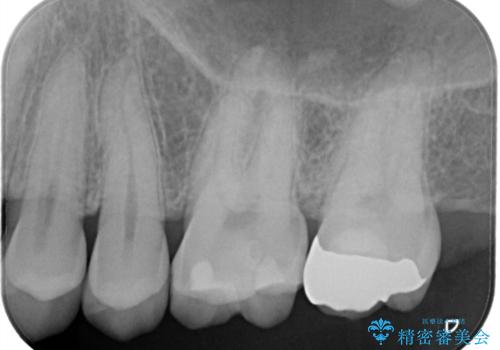

【セラミックインレー】歯科検診にて虫歯発見。

- 定期健診にて虫歯を見つけたためセラミックインレーにて修復しました。

綺麗に仕上がり患者さんも非常に満足されていました。

当院でのセラミックインレーはラバーダム防湿をして接着しております。